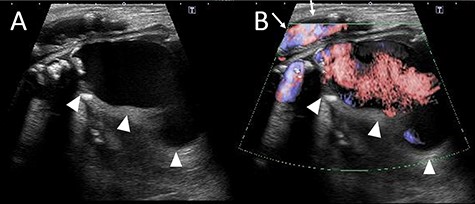

The patient looked pale but was conscious. He was thin and weighed 40 kg (body mass index, 14.5) due to loss of appetite after gastric surgery; however, his left thigh was reddish, edematous and painful (Fig. 1). Hemodynamics, such as blood pressure and heart rate, were stable. Blood tests revealed a hemoglobin level of 3.41 mmol/l. Ultrasonography showed a 72 × 52 mm PFAA with a thick thrombus and hematoma extending into the adductors (Fig. 2). A venous thrombus was also observed in the left femoral vein. Enhanced computed tomography (CT) revealed a ruptured left PFAA 64 × 54 mm in diameter (Fig. 3A and C). In addition, right iliac artery aneurysm and right CFA and SFA occlusion were also observed.

(A) Picture of the lower extremities of the patient. His left limb was edematous and hemostatic. (B) Picture of the left thigh. The patient’s thigh appeared reddish and had pain.